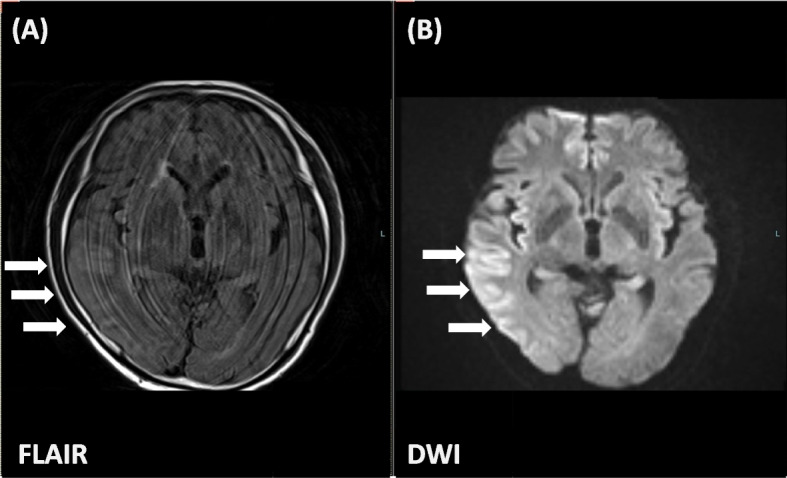

Non-convulsive status epilepticus (NCSE) is an electrical discharge which occurs without prominent motor symptoms. NCSE is one of the causes of delayed emergence from anesthesia; however, as far as we know, previous reports of postoperative NCSE were related to patients after neurological surgery. Herein, we report a case of an elderly male who developed initial NCSE after thoracic surgery. The patient remained unresponsive and developed hemiplegia after lung resection, and then the symptoms fluctuated between better and worse. Metabolic disorders and stroke were ruled out, and NCSE was diagnosed by magnetic resonance imaging (MRI) and electroencephalography (EEG). NCSE occurred in a patient who had no predisposing factors or underwent non-neurological surgery. When anesthesiologists encounter delayed emergence, NCSE should be listed as a differential diagnosis and examined by MRI and EEG.